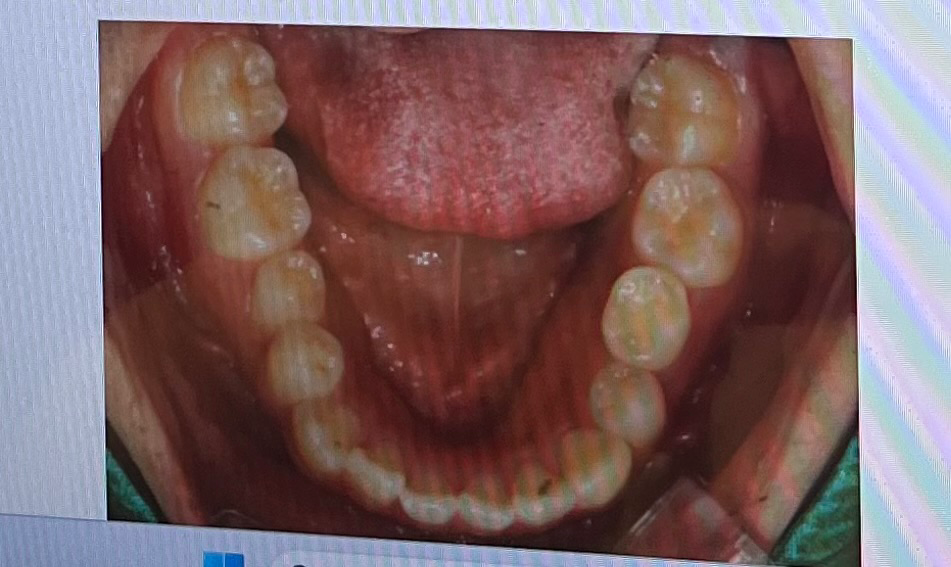

덧니가 심해서 교정 알아보고 있는 중인데요 두 군데 상담 다녀왔는데 한 곳에서는 상악악궁확장을 해야 한다고 하시고 한 곳에서는 굳이 악궁확장 안해도 충분히 할 수 있다고 하시는데 아무리 정보를 찾아봐도 잘 모르겠어서 질문드려요ㅠㅠ

두 곳 다 윗니 두 개 발치 해야 한다고 했고 그 외 상담 내용들도 똑같아서 악궁확장을 진짜 해야 하는건지 안해도 되는건지만 알면 병원 결정하기 쉬울 거 같아요 도와주세욥!!

• 1번 째 사진

• 2번 째 사진